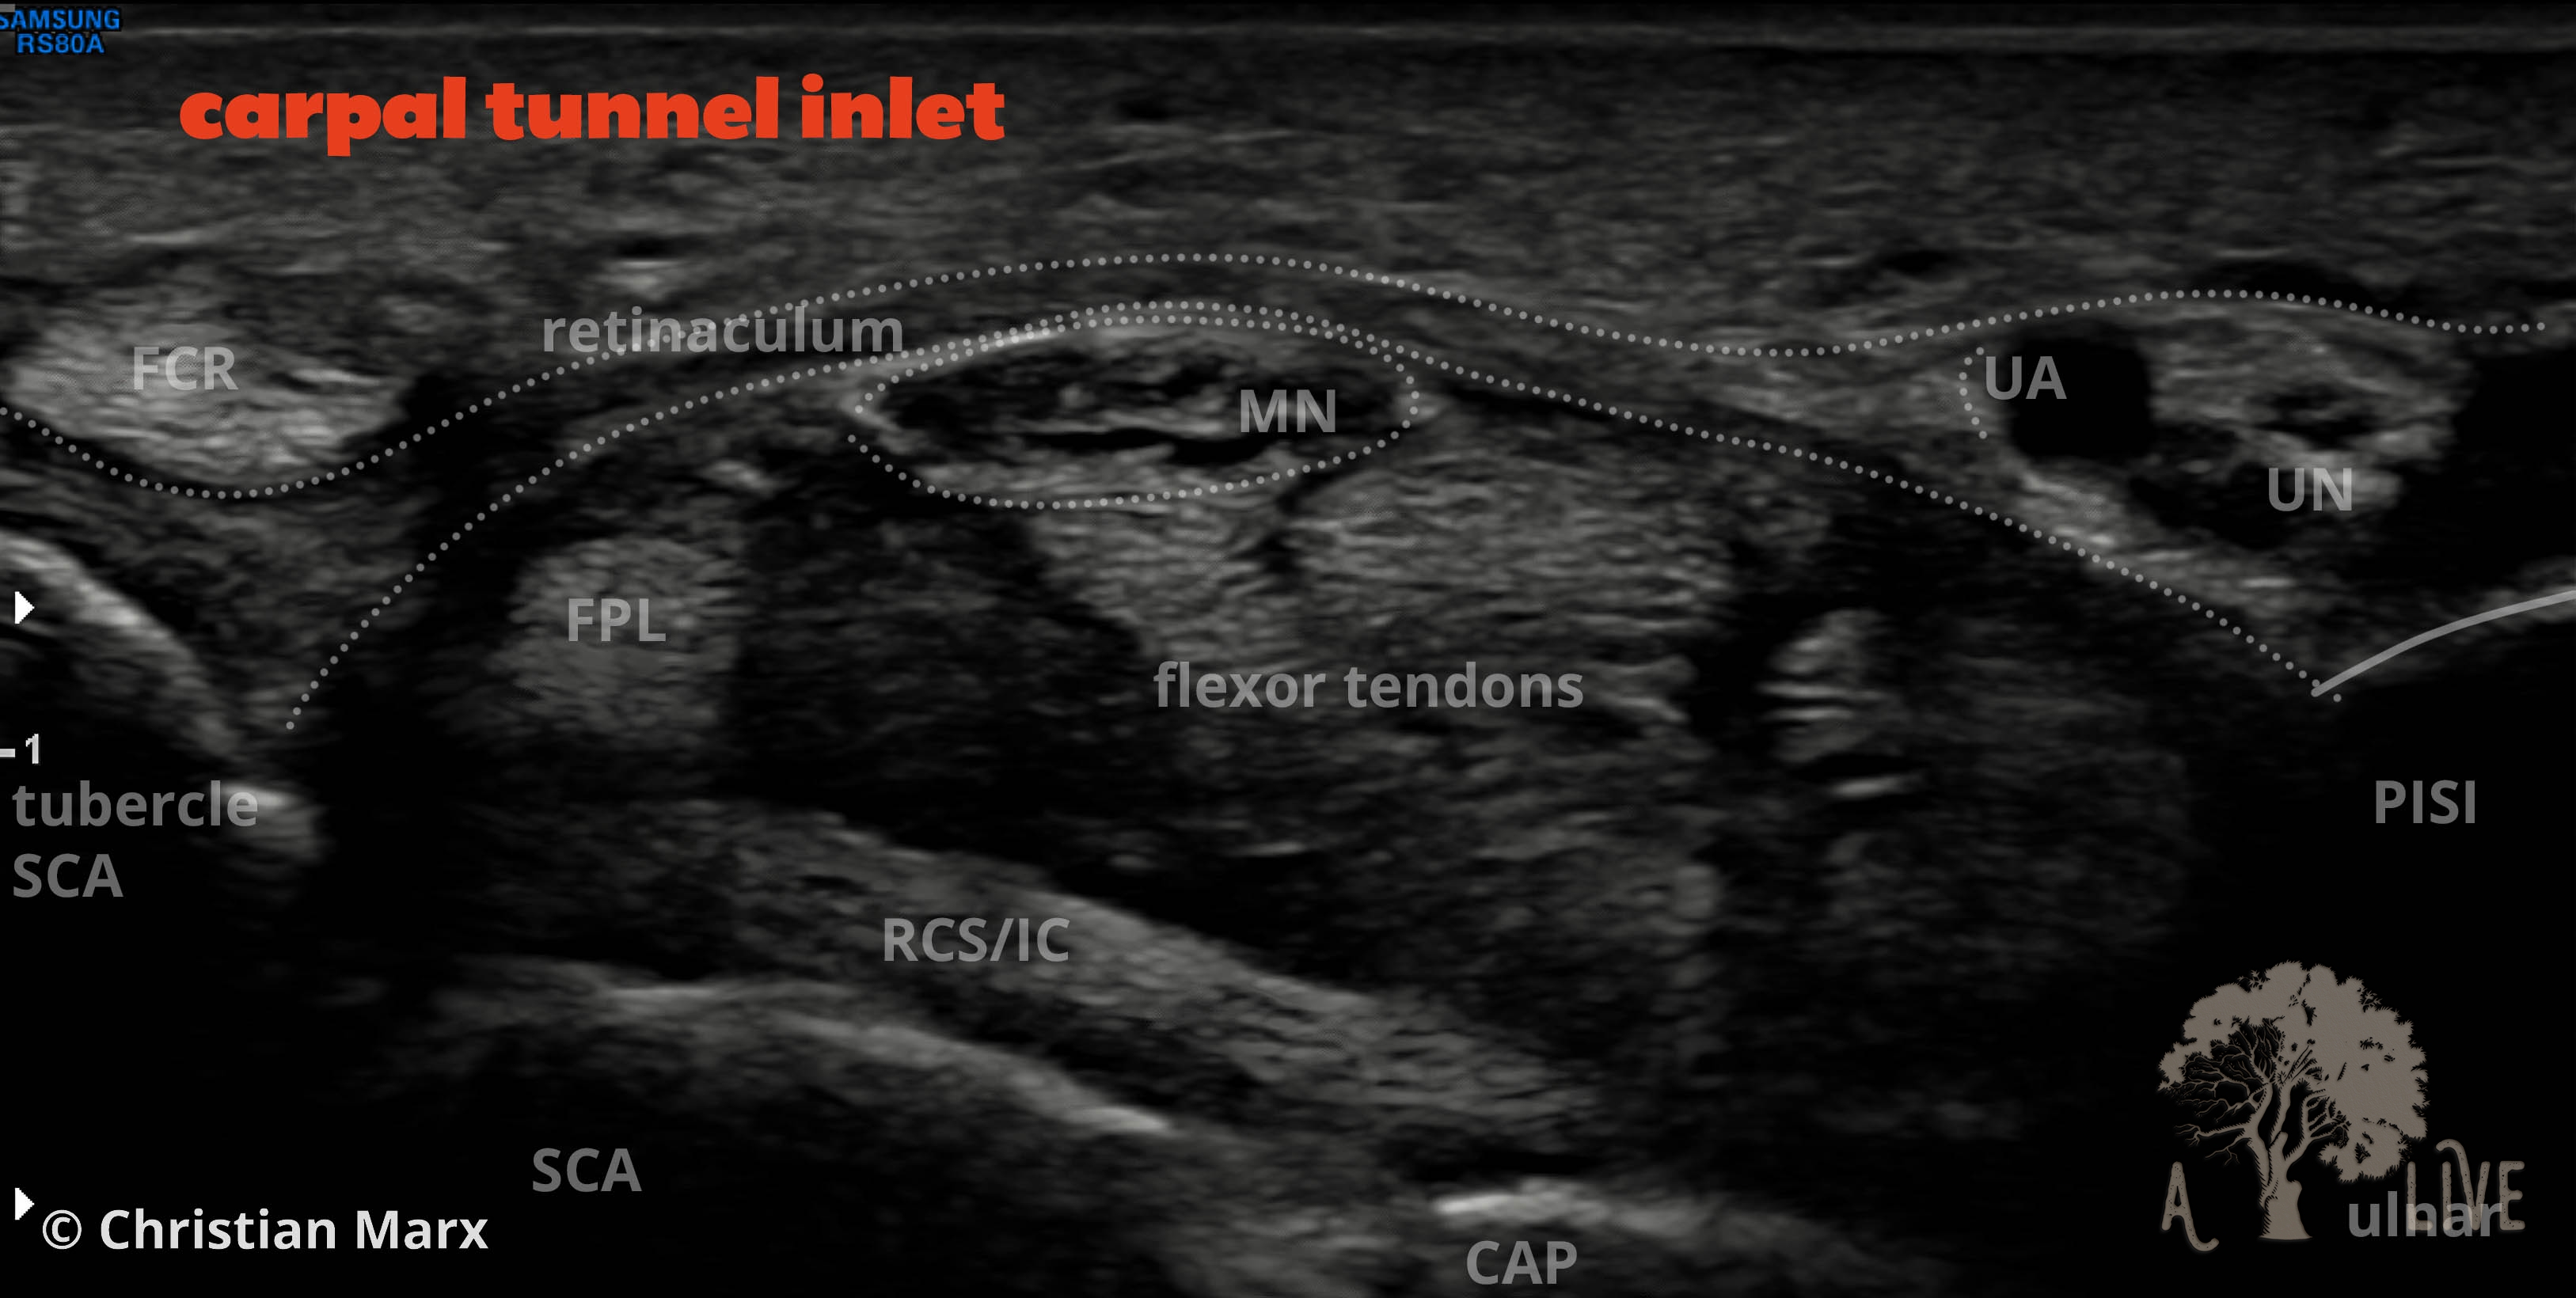

nerves of the hand region